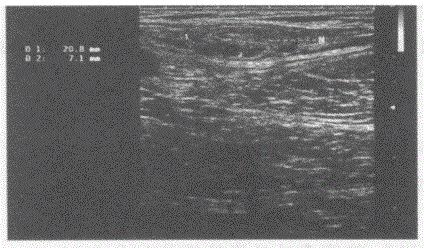

问题 临床资料:男,40岁,常规体检。 超声综合描述:右颈部可见数个长圆形低回声,边界清晰,部分融合。 超声提示:

选项 A.右颈部多发肿大淋巴结 B.右颈部淋巴结转移瘤 C.右颈部正常淋巴结声像图 D.右颈部淋巴结结核

答案 A